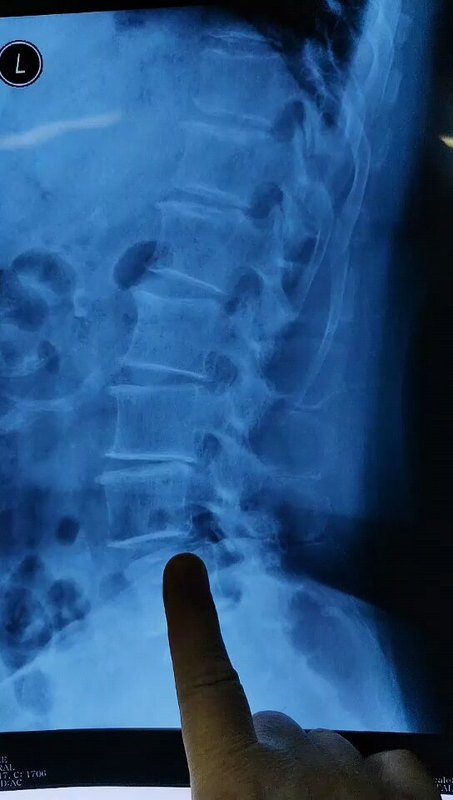

【医学科普】吓人的脊柱“拼接”片

江晓兵主任医师 广医二院 骨外科 脊柱外科

362人已读